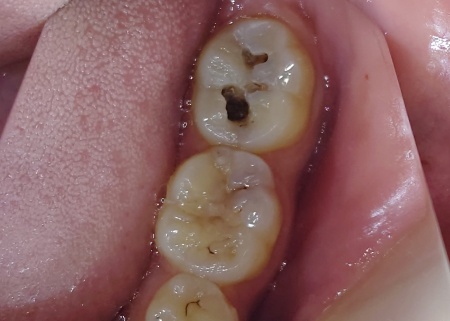

20代男性 左下奥歯の虫歯を除去し保険診療のコンポジットレジンで修復した症例

「左下奥歯が黒い気がする。痛みはないが、気になるので診てほしい」とご相談いただきました。

拝見したところ、左下奥歯の表面に黒い変色が見られたため、詳しく検査を行った結果、虫歯であることがわかりました。

痛みはないとのことでしたが、虫歯は必ずしも痛みを伴うとは限らず、症状がない段階でも歯の内部で進行していることがあります。

このまま放置すると、虫歯が進行して歯の神経にまで達し、強い痛みが出たり歯の神経を除去しなければならなくなったりするリスクがあります。

その際、黒く変色している部分を慎重に確認しながら進めましたが、一部は表面が滑らかで硬い状態であったため、細菌感染が及んでいないと判断し、削らずに残しました。

削らずに残した部分はやや黒ずんでいるため、コンポジットレジンの色合いと差が生じるおそれがあります。この点については、患者様に了承いただきました。